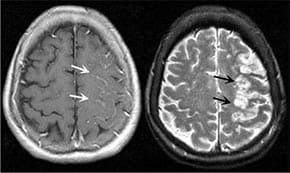

Да подобрите притока на кръв към главния мозък